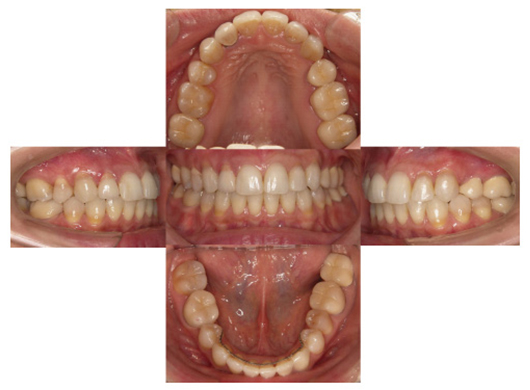

治療前-治療後

(治療後:写真右)

矯正治療をおこない歯列を整え、金属の詰め物はセラミッククラウンに換えて咬み合わせを再構成しました。

そして矯正治療後、初診時の様々な訴えは解消しました。